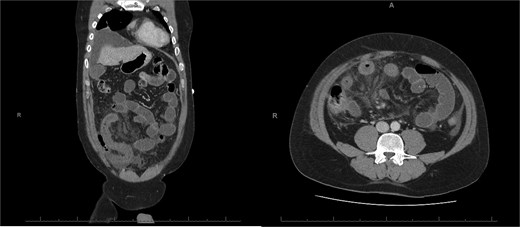

A 76-year-old female with a 3-day history of left upper abdominal pain, vomiting, and haematochezia. Her history included pulmonary embolism, multiple deep vein thromboses, with no ongoing anticoagulation, and an open partial colectomy for complicated diverticulitis a decade earlier. On admission, she was afebrile but tachycardic and showed localized tenderness in the left hypochondrium. Laboratory revealed leucocytosis with a white blood cell count (WBC) of 12 G/L, elevated C-reactive protein (CRP) of 46 mg/L, and hyperlactatemia of 2.6 mmol/l. Enhanced computed tomography (E-CT) revealed jejunal venous ischemia in the left upper quadrant, secondary to extensive porto-mesenteric thrombosis with reduced bowel wall enhancement, distention, and free intraperitoneal fluid (Fig. 1). She was managed conservatively with unfractionated heparin (UFH) with a bolus of 5000 U/l followed by 30 000 U/l/24 h (target INR 0.35–0.7), Piperacillin-Tazobactam, and bowel rest. After 48 h of monitoring in the intensive care unit (ICU), she exhibited marked biological and clinical improvement. E-CT on the third day showed restored bowel wall enhancement and stable porto-mesenteric thrombosis (Fig. 2). She was discharged on therapeutic low molecular weight heparin (LMWH) with enoxaparin sodium 120 mg every 12 h. At the 3-month follow-up, E-CT revealed near-complete thrombus resolution, without intestinal sequelae (Fig. 3).

Follow-up E-CT 72 h after conservative management in the first patient. Dashed arrows show improved viability of the small bowel with bowel wall enhancement. White arrows revealed the stability of the extended porto-mesenteric thrombosis.